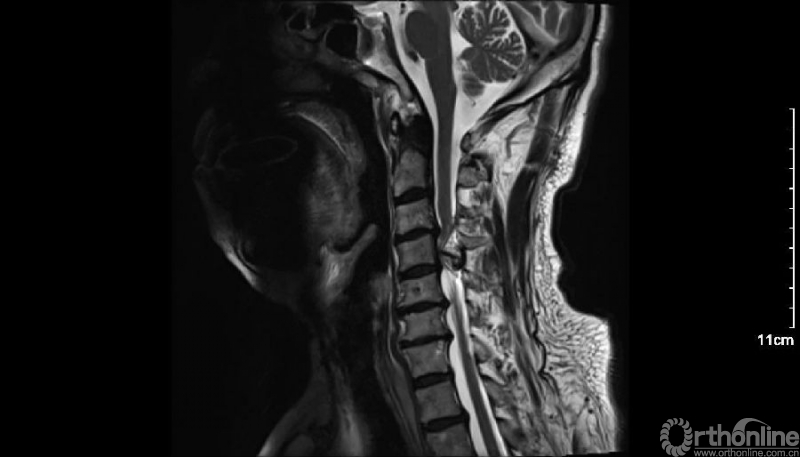

入院查体患者四肢肌张力高,双侧hoffman阳性。CT及MRI检查提示C4/5左侧关节突内缘有一巨大骨块(15mm*16mm),相应节段椎管严重狭窄。椎管内骨块的前端还有一游离骨块。

影像学资料